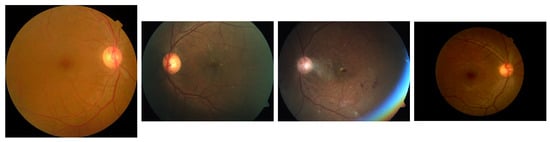

The APTOS [43] dataset represents a significant public resource for DR classification, made available through Kaggle competitions. Comprising approximately 3662 fundus images with diverse resolutions and quality levels, this dataset classifies DR severity into five stages (0∼4) based on the Early Treatment Diabetic Retinopathy Study (ETDRS) [59] criteria and is widely adopted in DR classification research. The APTOS labeling system follows a straightforward structure: No DR (0), Mild DR (1), Moderate DR (2), Severe DR (3), and Proliferative DR (4). The class distribution within the APTOS dataset is illustrated in Figure 1a. Examples of fundus images from the APTOS are illustrated in Figure 2.

The NMC dataset is a local dataset for DR classification distinguished by its multi-label structure incorporating detailed lesion information. Unlike APTOS, this dataset captures the direct cause of DR through comprehensive lesion-centered labeling by experienced ophthalmologists. The data was collected from subjects of various ages and both genders, ensuring demographic diversity. Images were captured using a KOWA Nonmyd-7 fundus camera fixed at positions optimized for examination, and was used for both mydriatic and non-mydriatic examinations. The images were taken by three different examiners in rotation, while the labeling of all fundus photographs was exclusively conducted by a single designated ophthalmologist to ensure consistency. The NMC dataset was collected and annotated under the approval of the Institutional Review Board of National Medical Center (Approval Code: NMC-2024-03-034, 28 March 2024) in accordance with the Declaration of Helsinki. Patient informed consent was waived due to the retrospective nature of the study using fully anonymized retinal images. Comprising approximately 6500 high-resolution fundus images with varying quality, the NMC dataset allows multiple labels per image. The labeling system categorizes various DR lesion conditions, as detailed in Table 2. After excluding labels 8, 9, and 10 (which do not impact DR classification) and removing noisy labels (where normal and DR conditions coexist), the final dataset contains approximately 6000 samples with 27 unique label combinations. Figure 1b presents the frequency distribution of these class combinations. The NMC dataset is anonymized to ensure that all patient identification information is removed, complying with ethical standards for medical data usage. Examples of fundus images from the APTOS are illustrated in Figure 3.